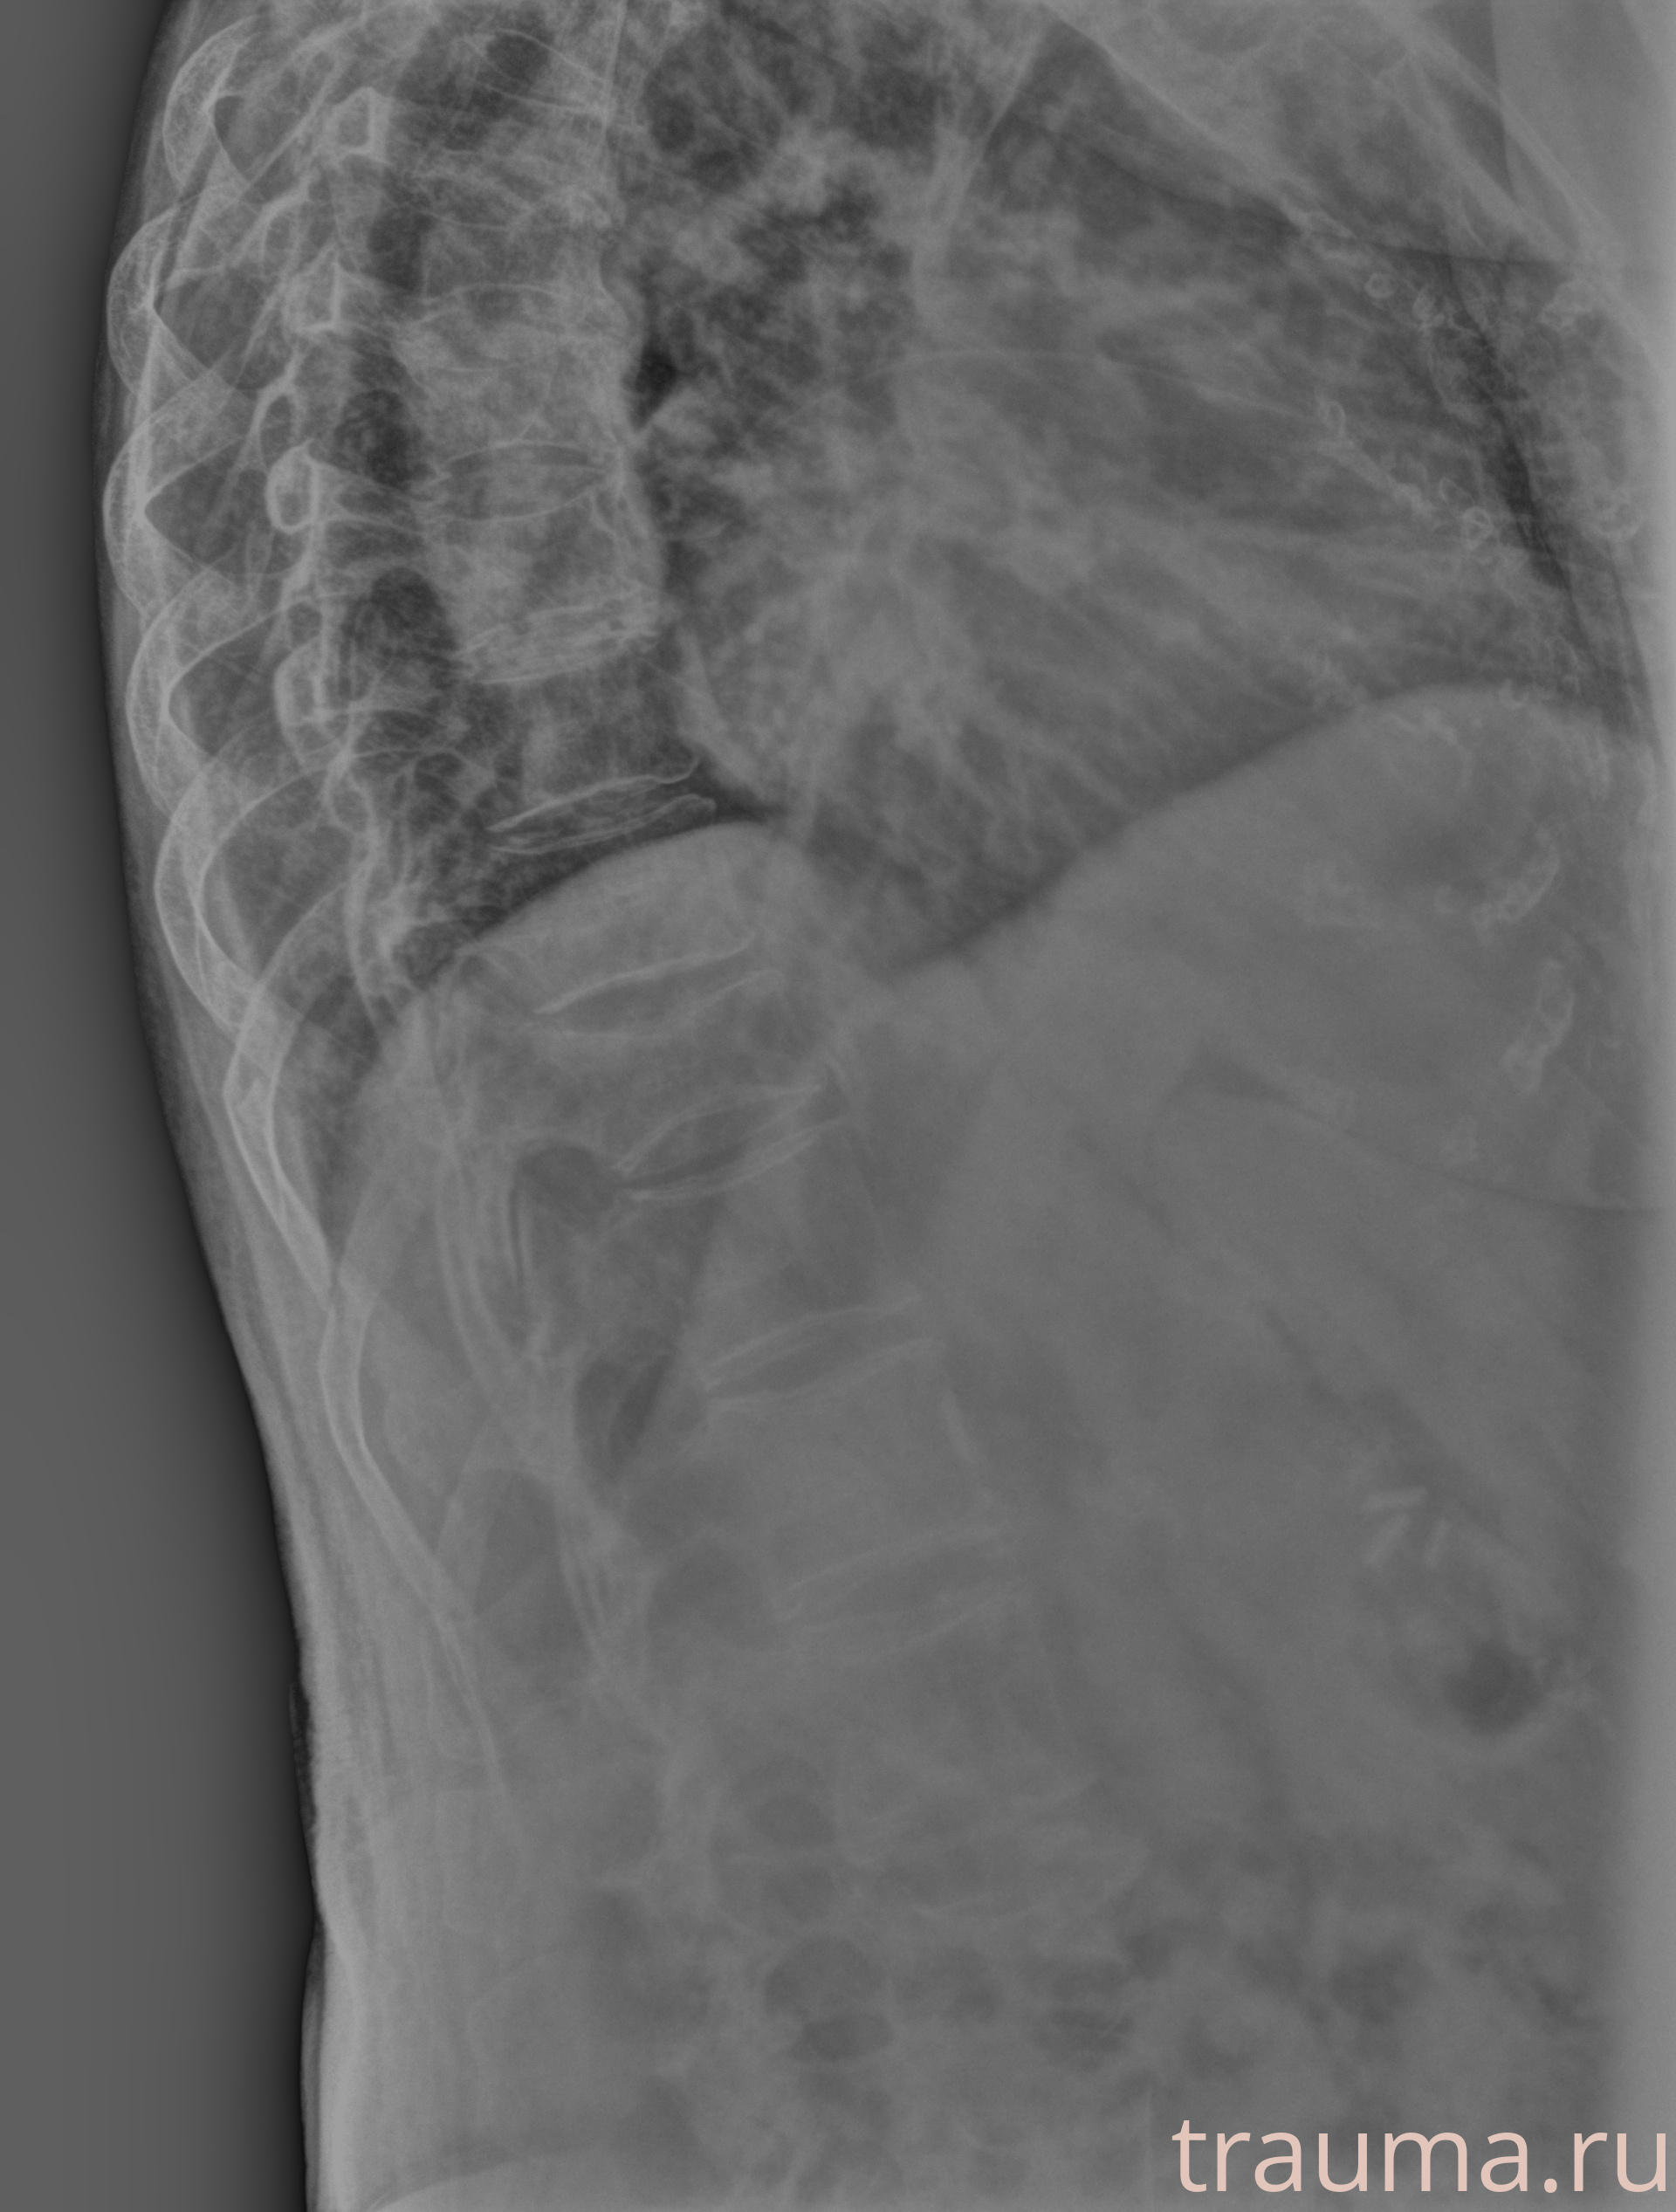

Рентген на дому: по вашему адресу приезжает врач-рентгенолог, травматолог-ортопед с мобильным рентгеновским аппаратом, проводит диагностику травмы или заболевания, делает необходимые рентгенограммы, дает рекомендации по дальнейшему лечению. Получить качественные снимки в домашних условиях возможно благодаря уникальной методике, разработанной МосРентген Центром для института  Склифосовского